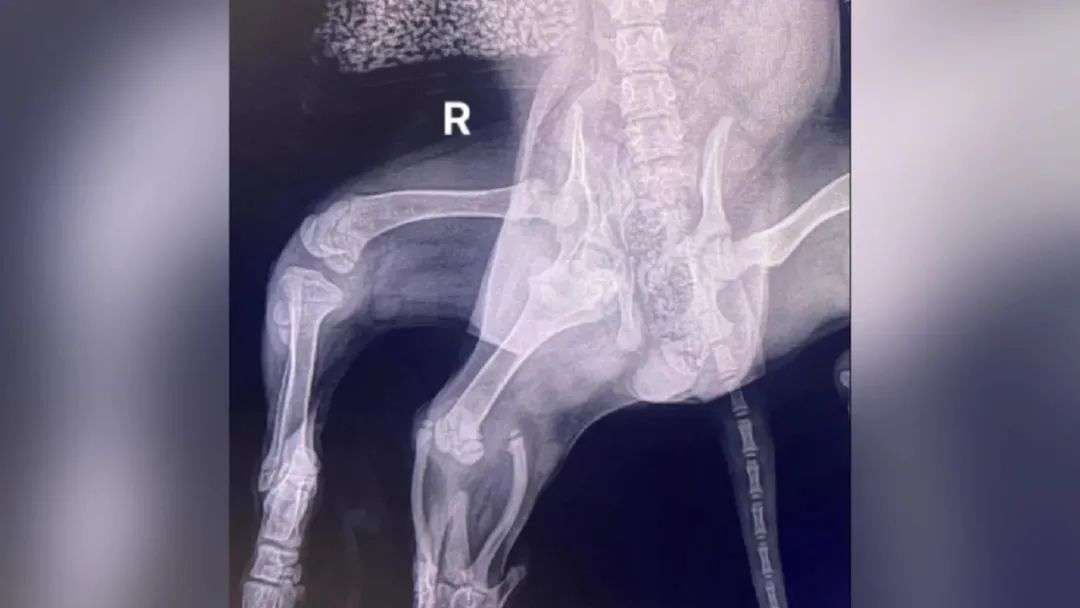

救助中心的工作人员带它去宠物医院做了一次全面的检查,发现它的问题还不少,除了多出来的两条腿外,它还多了一个外阴,少了一颗肾脏,有两个子宫以及更多的血管。

它后半身骨骼发育畸形,身体一侧长有两个髋关节,骨盆发育不完全,虽说目前不耽误行动,可时间一长还是会造成身体损伤,必须要把附着在上面那两条多余的腿切除才行。

然而,它右侧那条正常的后腿又肌张力过低,一旦做了手术,这条好腿可能也会被截掉,反正治疗起来非常棘手……

(爱丽儿的X光照片)